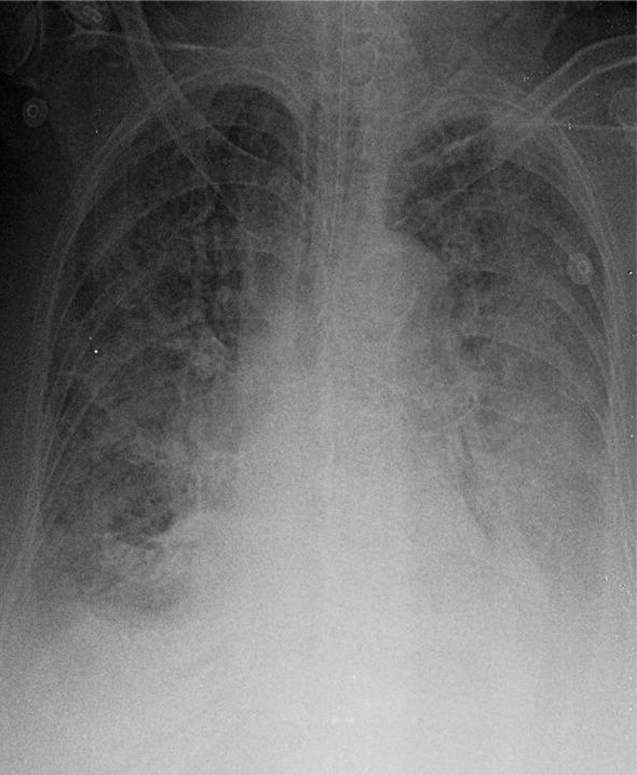

1-Thâm nhiễm phế nang lan tỏa hai phổi => Viêm phổi 2-Tràn dịch màng phổi hai bên 3-Cung động mạch chủ dãn